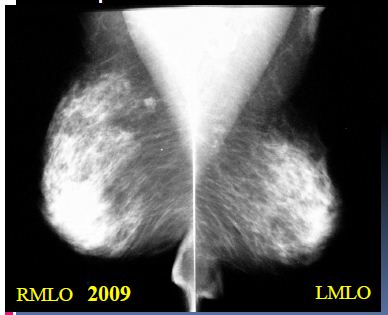

Kazuistika 2

- Klientka s nálezem nepravidelného zastínění při bazi sin

- Na kontrolním snímku správně zhotoveném není patrná

- Dobré vytažení!!! Komprese!!!